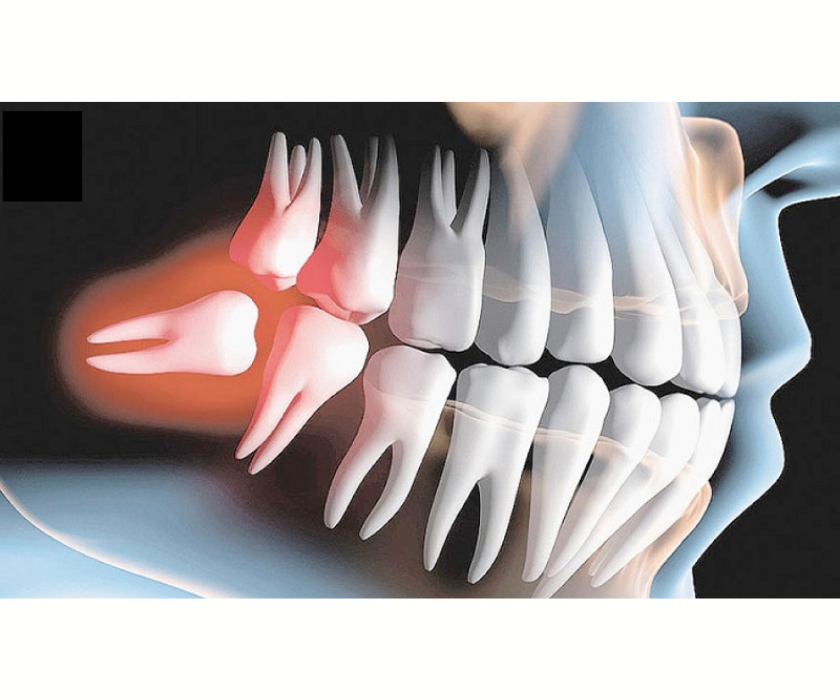

Răng khôn chèn ép có thể làm tiêu xương răng bên cạnh

Răng khôn chèn ép có thể làm tiêu xương răng bên cạnh

Tiêu xương ổ răng

Áp lực từ răng khôn mọc lệch khiến xương quanh răng số 7 bị tiêu dần, làm răng lung lay và giảm khả năng ăn nhai.